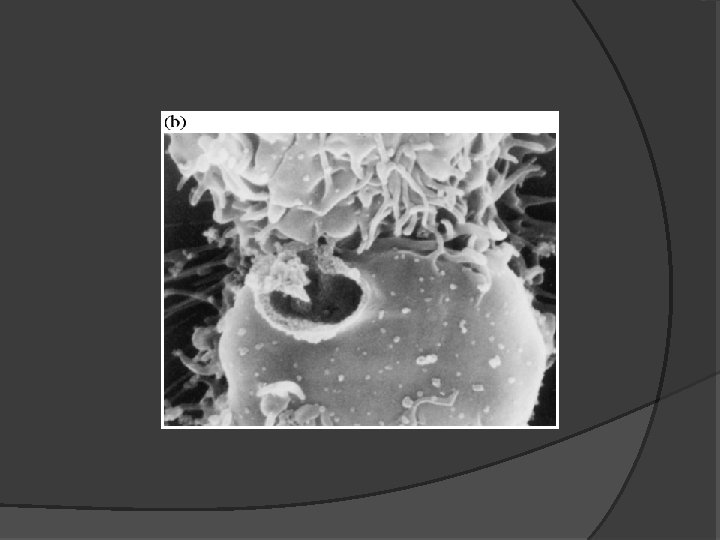

2. 3. ADCC---Antibody-Dependent Cell. Mediated. Cytotoxicity